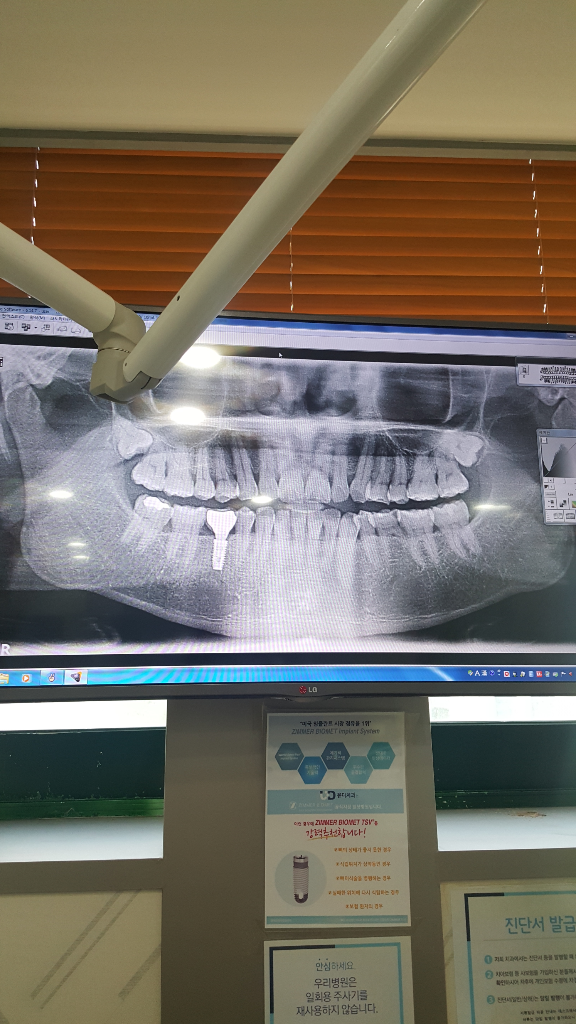

위쪽 사랑니는 특별히 발치를 안하셔도 될것같습니다. 지금 잇몸뼈에 뭍혀 잇기 떄문에 크게 문제가 될것같지 않습니다.

사랑니가 맹출되지않고 주변조직에 문제를 일으키지 않는다면 발치를 할 필요는 없습니다.

인접치아의 치근을 흡수하는등의 문제가 생길 가능성이 있기 때문에 웬만하면 뽑으시는 것이 좋습니다